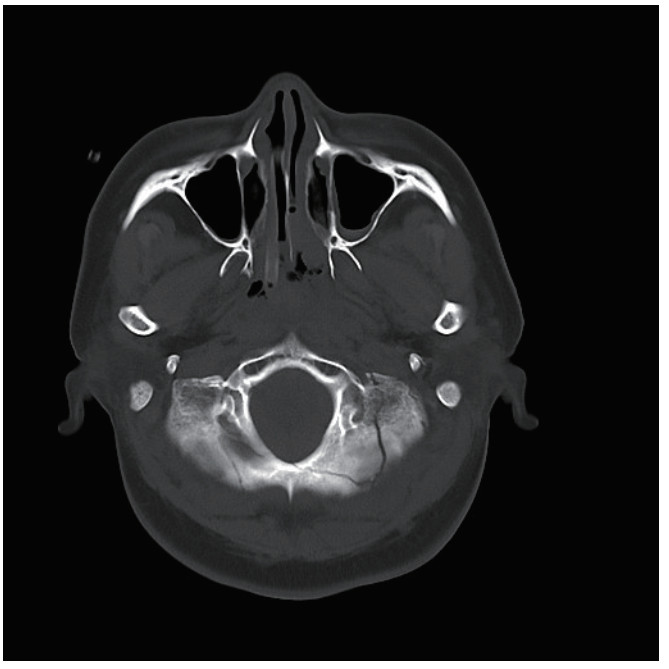

1 病例资料患者,女性,40岁,因“车祸致全身多处外伤半小时余”于2025年6月27日由120送入黄山市人民医院急诊。患者2 h前骑电瓶车发生车祸,致头面部、胸部及左下肢严重受伤,当即昏迷,伴恶心呕吐。入抢救室时自主呼吸微弱,后出现室速,伴随血流动力学不稳定,GCS评分为6分(E1V1M4),双侧瞳孔不等大、对光反射迟钝,左侧直径3 mm,右侧5 mm,后枕部头皮血肿,左下肢胫腓骨区域明显肿胀畸形。医院立即实施全面评估,经紧急行电复律、利多卡因静推后恢复自主心率,予以气管插管保护气道,建立深静脉通路泵入血管活性药物维持血压、纠正酸中毒。完善CT检查:双侧脑挫伤、创伤性蛛网膜下出血、右侧额顶部硬膜下血肿,中颅底及枕骨骨折、累及枕骨大孔,左侧胫腓骨骨折及双肺坠积性改变。见图 1,2。神经外科会诊诊断为弥漫性轴索损伤,无立即手术指征,收入EICU监护稳定生命体征。

| 图 1 脑挫伤伴出血 |